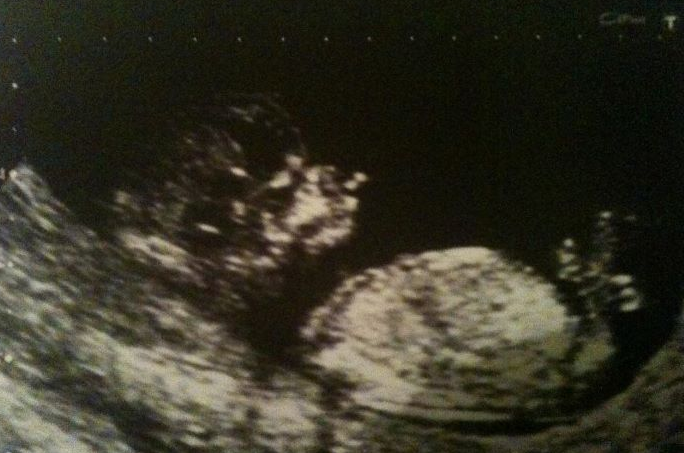

I have my 12 week scan on Monday, if mine and the midwifes calculations are right then it should say I'm 13+1 weeks. I'm hoping I'm in luck and I'm further on, I may cry if they give me anything less then 12. Just itching to get these first 15/16 weeks out of the way and get down to enjoying this pregnancy like I should be.